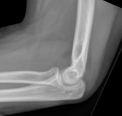

Los hallazgos pueden ser bastante sutiles y la única pista puede ser el signo de la almohadilla de grasa (sombras radiolúcidas triangulares anteriores y posteriores al húmero distal en la radiografía lateral, que indican hemartrosis y desplazamiento de la almohadilla de grasa intraarticular, a menudo asociado a una lesión esquelética intraarticular).

Imagen del signo de la almohadilla adiposa del codo (Hellerhoff (obra propia), vía Wikimedia Commons):

Signo de la almohadilla de grasa del codo

James Heilman, MD, CC BY-SA 4.0, vía Wikimedia Commons